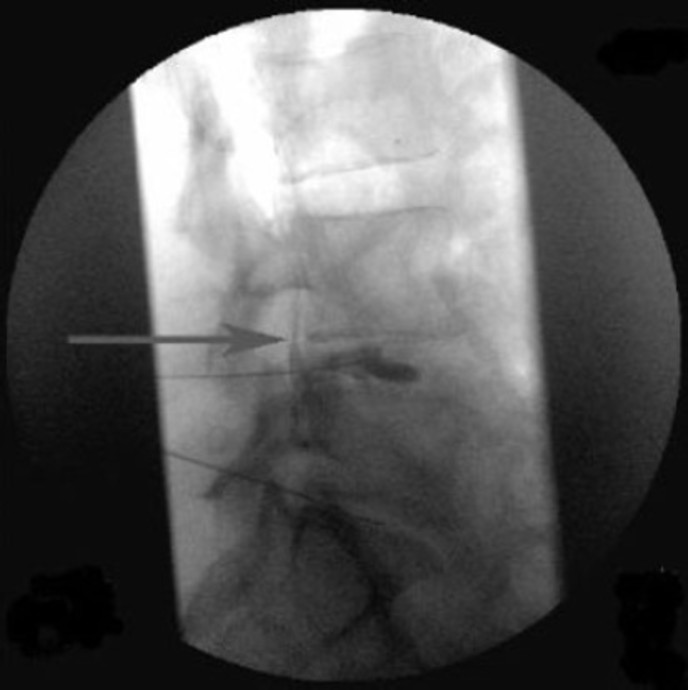

Fluoroscopically guided steroid injections are typically used to alleviate chronic spine, leg or arm pain. They are performed with continuous x-ray guidance to determine the proper placement of the injection. Lumbar epidural injections, facet joint injections and sacroiliac injections can all be performed fluoroscopically. An individual with persistent low back pain radiating from the back into the legs may be a candidate for one of these procedures.